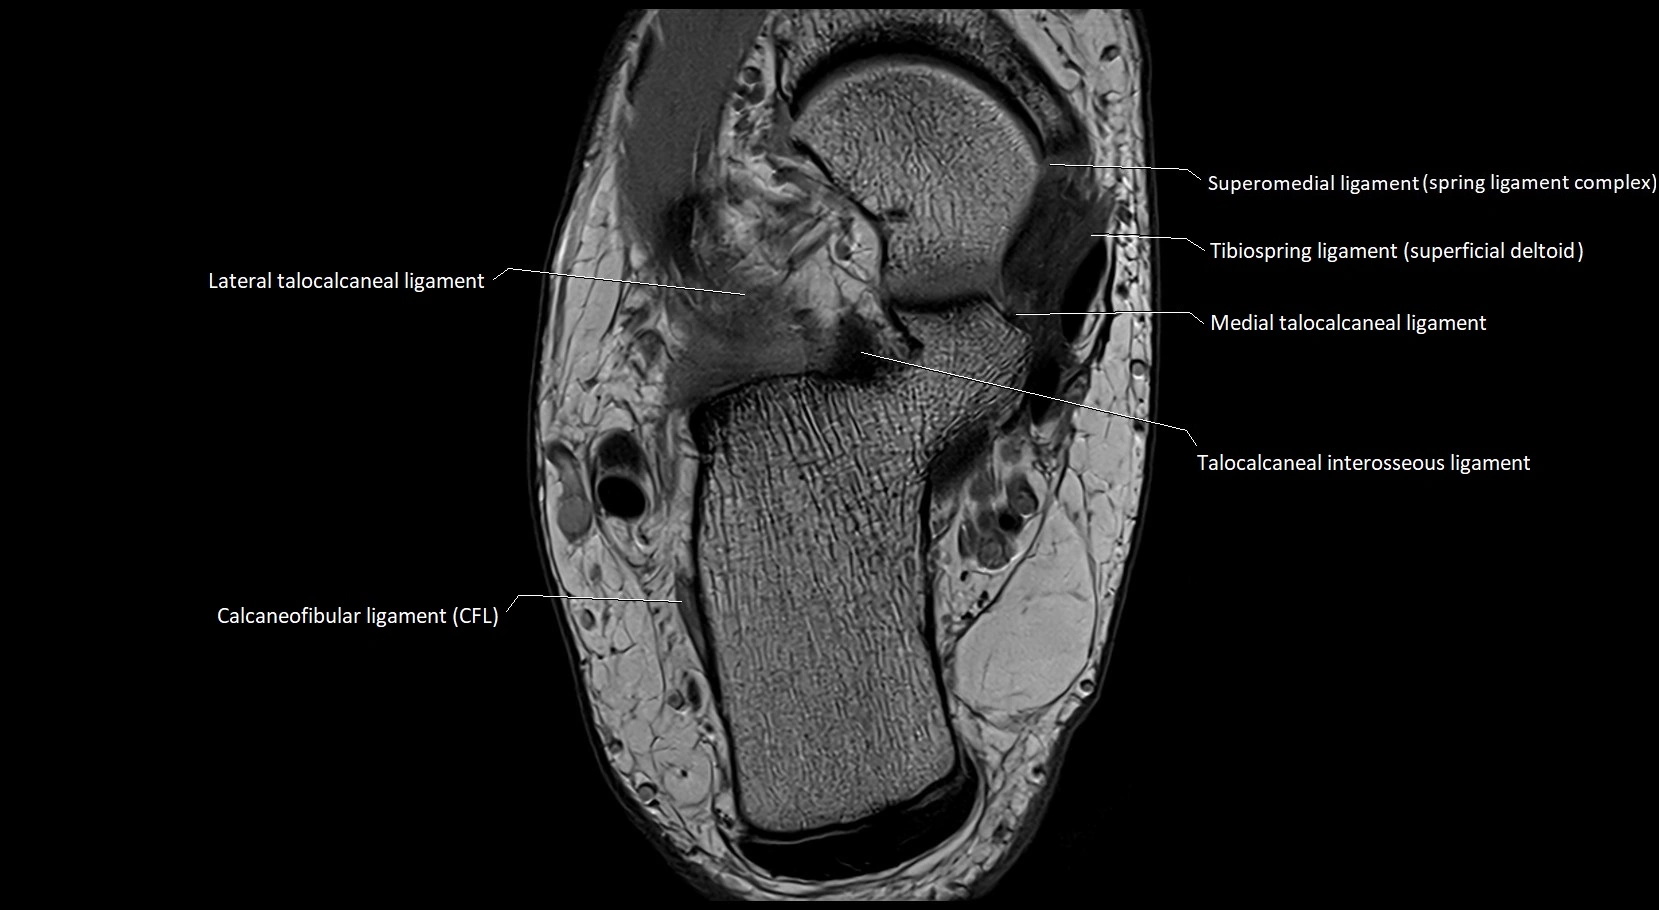

MRI image

image